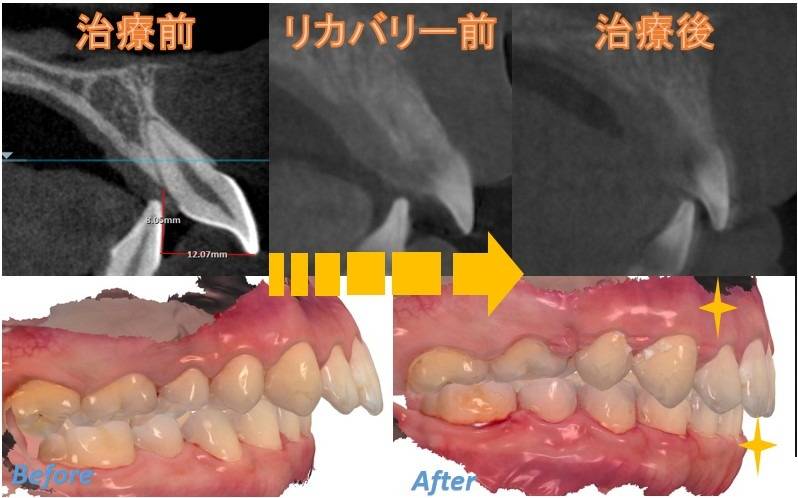

3. 「リカバリー治療保証」の詳細と適応条件

「リカバリー治療保証」は、単に「満足するまで何度でも」というサービスではありません。医療としての予知性を高め、客観的な基準に基づいて実施されるものです。

保証適応の客観的基準

セファロ分析による数値が基準値から一定以上乖離している場合

骨格性Ⅰ級であることなど、医学的な判断基準※1を設けています

条件1:セファロ分析上のオーバージェットの数値上の基準値から2mm以上乖離している

条件2:骨格性Ⅰ級であること

条件3:頭蓋正面において標準(MesoFacial)であること